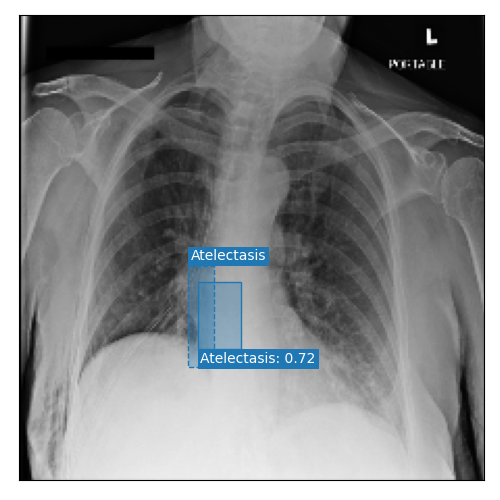

Qualitative Results

As shown in Fig. 4 Loc-ADPD detects cardiomegaly almost perfectly, as it is always exactly localized at one anatomical region. Other pathologies are detected but often with too large or too small boxes as they only cover parts of anatomical regions or stretch over several of them, which cannot be completely corrected using WBF. Detection also works well for predicting several overlapping pathologies. For qualitative comparisons between Loc-ADPD and MIL-ADPD, we refer to Appendix 0.B.